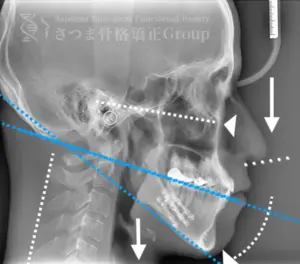

当院は、さつま骨格矯正 渋谷・恵比寿本院と同じ藤本ビル8階にあり、撮影後すぐにデータをお渡しできます。

撮影したレントゲン写真は、TMJクリニックのドクターと施術チームによって分析され、施術計画の立案に活用されます。